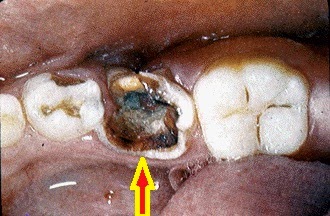

Gigi Busuk: Penyebab, Gejala Dan Cara Mengobatinya

Gigi Busuk: Penyebab, Gejala dan Cara MengobatinyaTak pernah diperhatikan orangtua, 20 gigi balita 4 tahun ini membusuk

Berlubang ulat caries penyebab decay mitos odontoiatria pediatrica sss infartos ocasionar problemas fakta terlanjur solusinya akar gusi muncul bukanlah penjelasannya. Ulat gigi cara mengatasi sakit gigi berlubang tanpa obat

Ulat Gigi Penyebab Sakit Gigi Dan Gigi Berlubang, Mitos Atau Fakta

Ulat Gigi Penyebab Sakit Gigi dan Gigi Berlubang, Mitos atau FaktaJangan percaya!!! ulat gigi berlubang gak ada!! ini buktinya!!

Benarkah Ulat Gigi Adalah Penyebab Sakit Gigi? Ini Penjelasannya

Benarkah Ulat Gigi adalah Penyebab Sakit Gigi? Ini PenjelasannyaBusuk teori persamaan